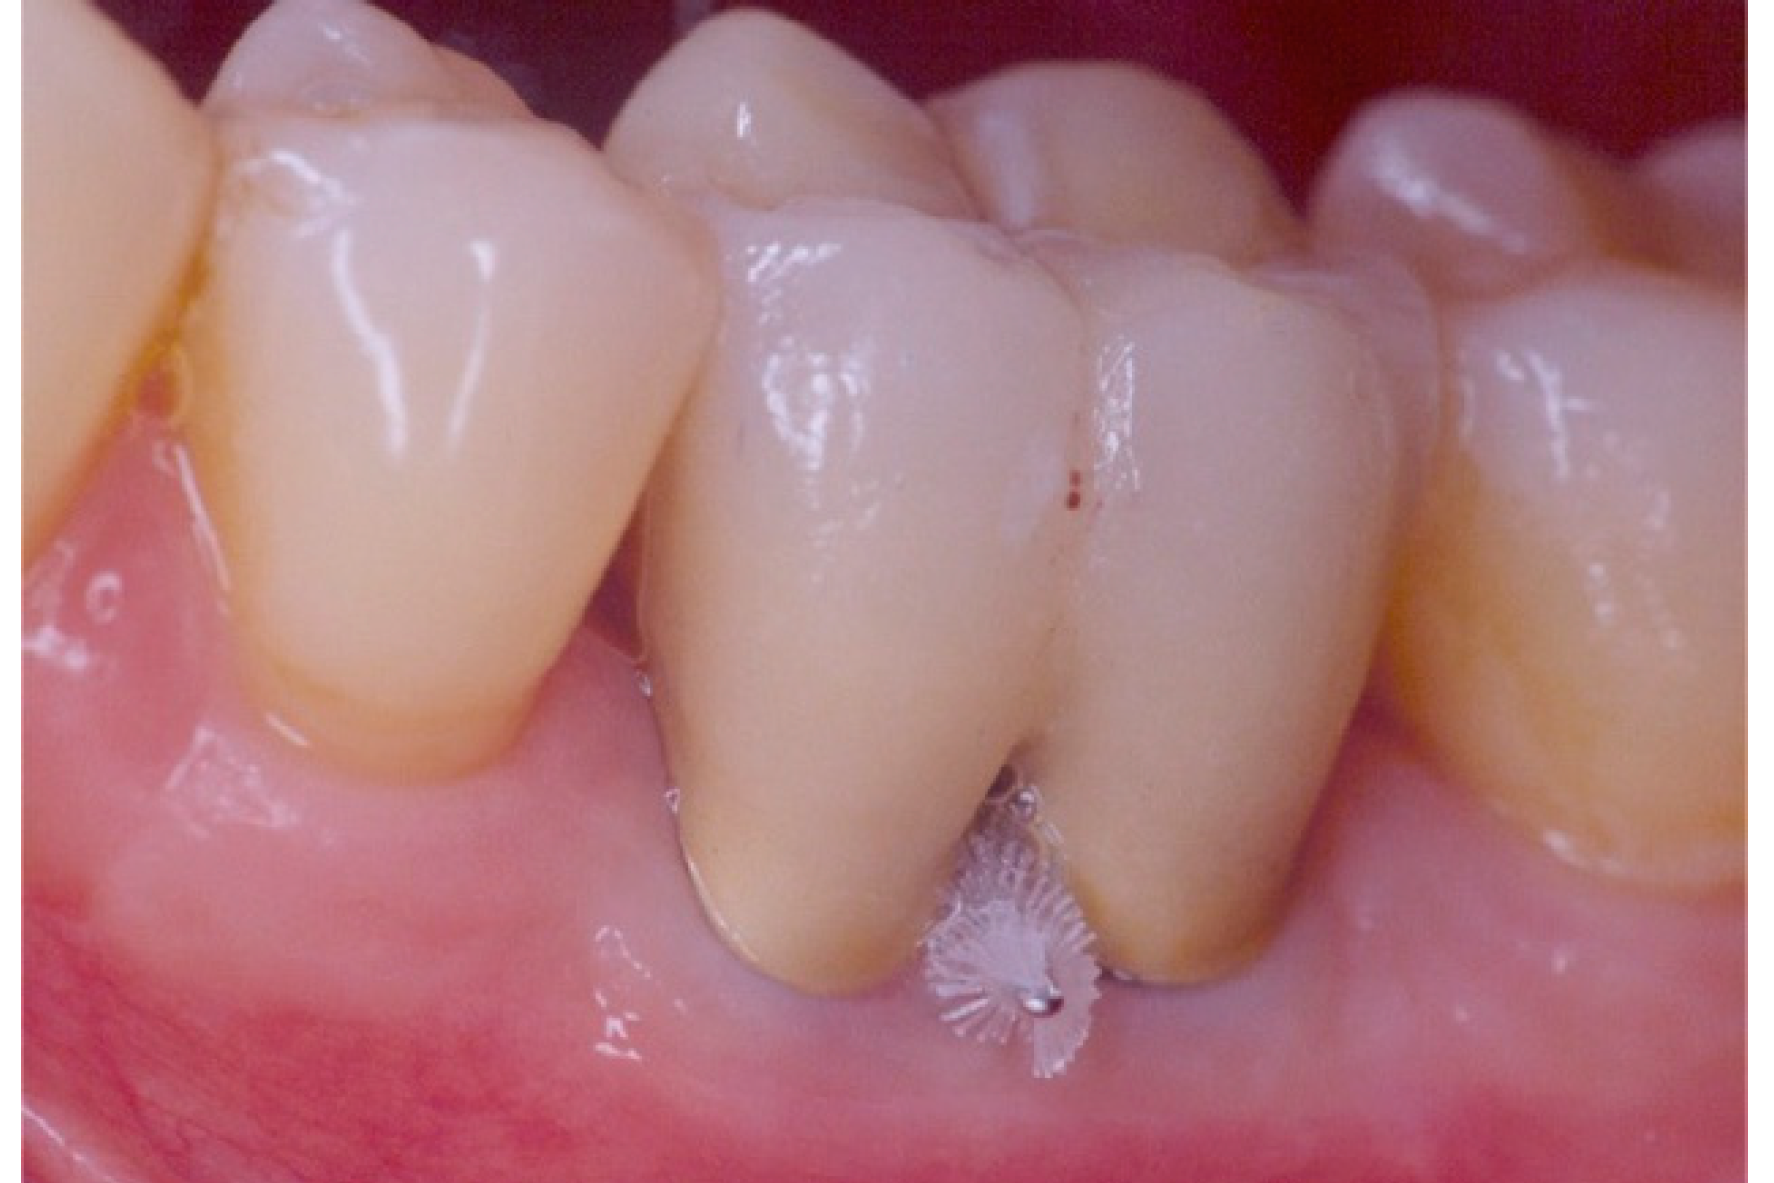

Furkacja odgrywa ważną rolę w codziennej pracy, ponieważ stanowi obszar trudny do oczyszczania. Płytka bakteryjna oraz kamień nazębny łatwo gromadzą się w tym miejscu, dlatego nawet prawidłowa higienizacja domowa bywa niewystarczająca. Z tego powodu stomatolog często zaleca regularne zabiegi higienizacji w klinice, aby ograniczyć ryzyko zapalenia dziąseł i przyzębia.

Jeżeli w obrębie furkacji dojdzie do utraty kości, pojawia się tzw. defekt furkacyjny. Taki stan może utrudniać leczenie kanałowe, a także obniżać rokowanie dla zęba. Dlatego wczesna diagnostyka ma kluczowe znaczenie.